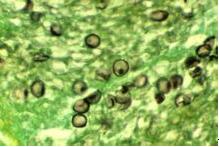

卡氏肺孢子菌

一、發(fā)病特點:肺孢子菌病是由卡氏肺孢子菌引起的呼吸系統(tǒng)機會感染?ㄊ戏捂咦泳w寄生在肺泡內(nèi),其臨床特征為發(fā)熱、于咳、呼吸急促、呼吸困難和發(fā)紺等,癥狀呈進行性加劇,

病死率高?ㄊ戏捂咦泳鷱V泛存在于人和某些哺乳類動物肺組織內(nèi)。隱性、亞臨床或潛在性感染相當多見。血清流行病學調(diào)查顯示多數(shù)健康兒童幼年曾與原蟲接觸,2/3以上可檢得IgG抗體;與病人接觸的醫(yī)務(wù)人員中7%~15%抗體效價升高。病人和隱性感染者為本病傳染源,主要通過空氣飛沫傳播。健康人感染后一般不發(fā)病,本病呈世界性分布。